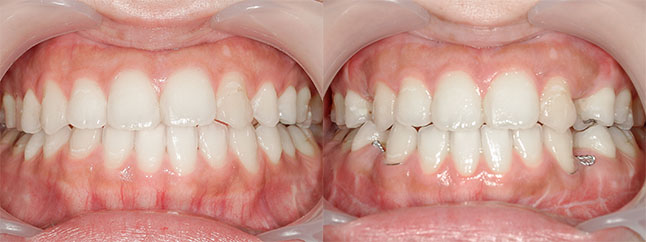

【治療内容】出っ歯、口元の膨らみが気になると当院を受診されました。上の前歯と歯茎が前方にポジショニングしており、下の前歯も歯茎から前に出ておりました。

<上下セットバック>

歯と歯茎を上は、5oバック、2oアップ、下は5oバックし固定しました。

※口ゴボ感が改善し、ご満足いただけました。

※afterは術後3か月時の写真です。

【費用】上下セットバック 2,307,800円(税込)

【リスク】感染・腫れ・出血・知覚鈍麻など